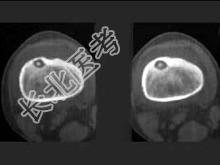

- 单项选择题男,36岁, 左大腿疼痛,夜间疼痛加剧, 结合所提供的图像,最可能的诊断是 ( )

A、良性骨母细胞瘤

B、骨样骨瘤

C、骨纤维异常增殖症

D、纤维性骨皮质缺损

E、非骨化性骨纤维瘤